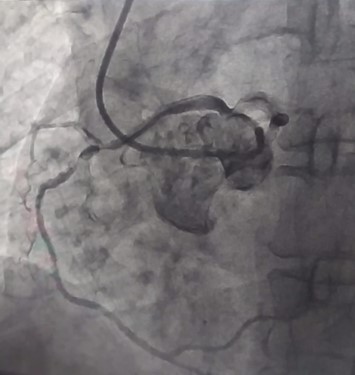

ووقام الفريق الطبى بقسم طب القلب والقسطرة والذي ضم الدكتور مؤمن لطفي مدرس طب القلب والأوعية الدموية والدكتور اسلام راشد مدرس مساعد بقسم القلب بإنقاذ حياة مريضة تبلغ من العمر 40 عاما، تعاني من وجود عيب خلقي في بداية غير طبيعية بالشريان التاجي الأيمن وتم عمل قسطرة علاجية بالتصوير التشخيصي للشريان الأيسر، وأمكن استخدام نفس القسطرة كقسطرة علاجية بعد أن قام الفريق المعالج بإجراء تعديلات لتركيب الدعامة في الشريان الايمن وتم إنقاذ حياة المريضة بنجاح.